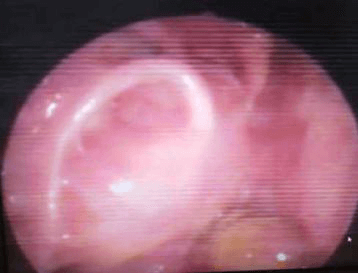

তিনি প্রথমে যশোদা হাসপাতালে ওপি হিসাবে এবং পরে স্থানীয় ইএনটি-এর সাথে অনুসরণ করেছিলেন। দুই বছর পর তার আমাদের সফরের সময় পুনরাবৃত্তির কোনো প্রমাণ পাওয়া যায়নি। এখন তিনি এপ্রিল মাসে আমাদের কাছে উপস্থাপন করেছিলেন যে এক সপ্তাহের জন্য ডান দিকের নাক দিয়ে রক্তপাত হচ্ছে। DNE ডানদিকে একটি অনিয়মিত মসৃণ পৃষ্ঠ ভাস্কুলার ভর দেখিয়েছে। CT PNS অনুনাসিক গহ্বরের পিছনের অংশে নরম টিস্যু ভর দেখায় যা ছাদ পর্যন্ত প্রসারিত হয় (ক্রিব্রিফর্ম প্লেট) এবং উপরে স্ফেনয়েড সাইনাস এবং নীচে নাসোফ্যারিনক্স পূরণ করে। তাকে রেডিওথেরাপি বিভাগে রেফার করা হয়েছিল যেখানে তাকে মস্তিষ্ক এবং কক্ষপথের নৈকট্যের কারণে IMRT-এর পরামর্শ দেওয়া হয়েছিল।